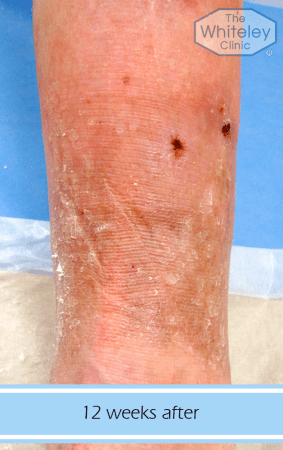

A venous leg ulcer patient - 12 weeks post treatment

Please note, these images are of a clinical nature which some people might find upsetting. Click on each icon below to open the images.